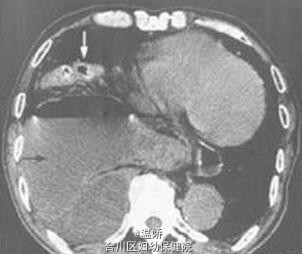

巨大食管裂孔疝嵌顿一例

男性,84岁。因“餐后突发右侧胸闷胸痛3d”来院求治。疼痛为持续性,伴恶心,无呕吐及发热。发病以来仅能进少量流质,排大便1次。既往有冠状动脉粥样硬化性心脏病史10余年,5年前曾因食管裂孔疝经左胸行疝修补术。

巨大食管裂孔疝。